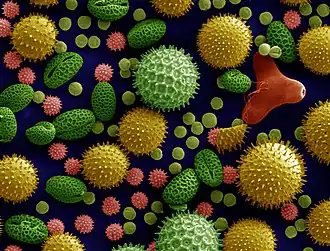

| SEM Microscope image of Pollen grains from a variety of common plants: sunflower (Helianthus annuus), morning glory (Ipomoea purpurea), prairie hollyhock (Sidalcea malviflora), oriental lily (Lilium auratum), evening primrose (Oenothera fruticosa), and castor bean (Ricinus communis). | |